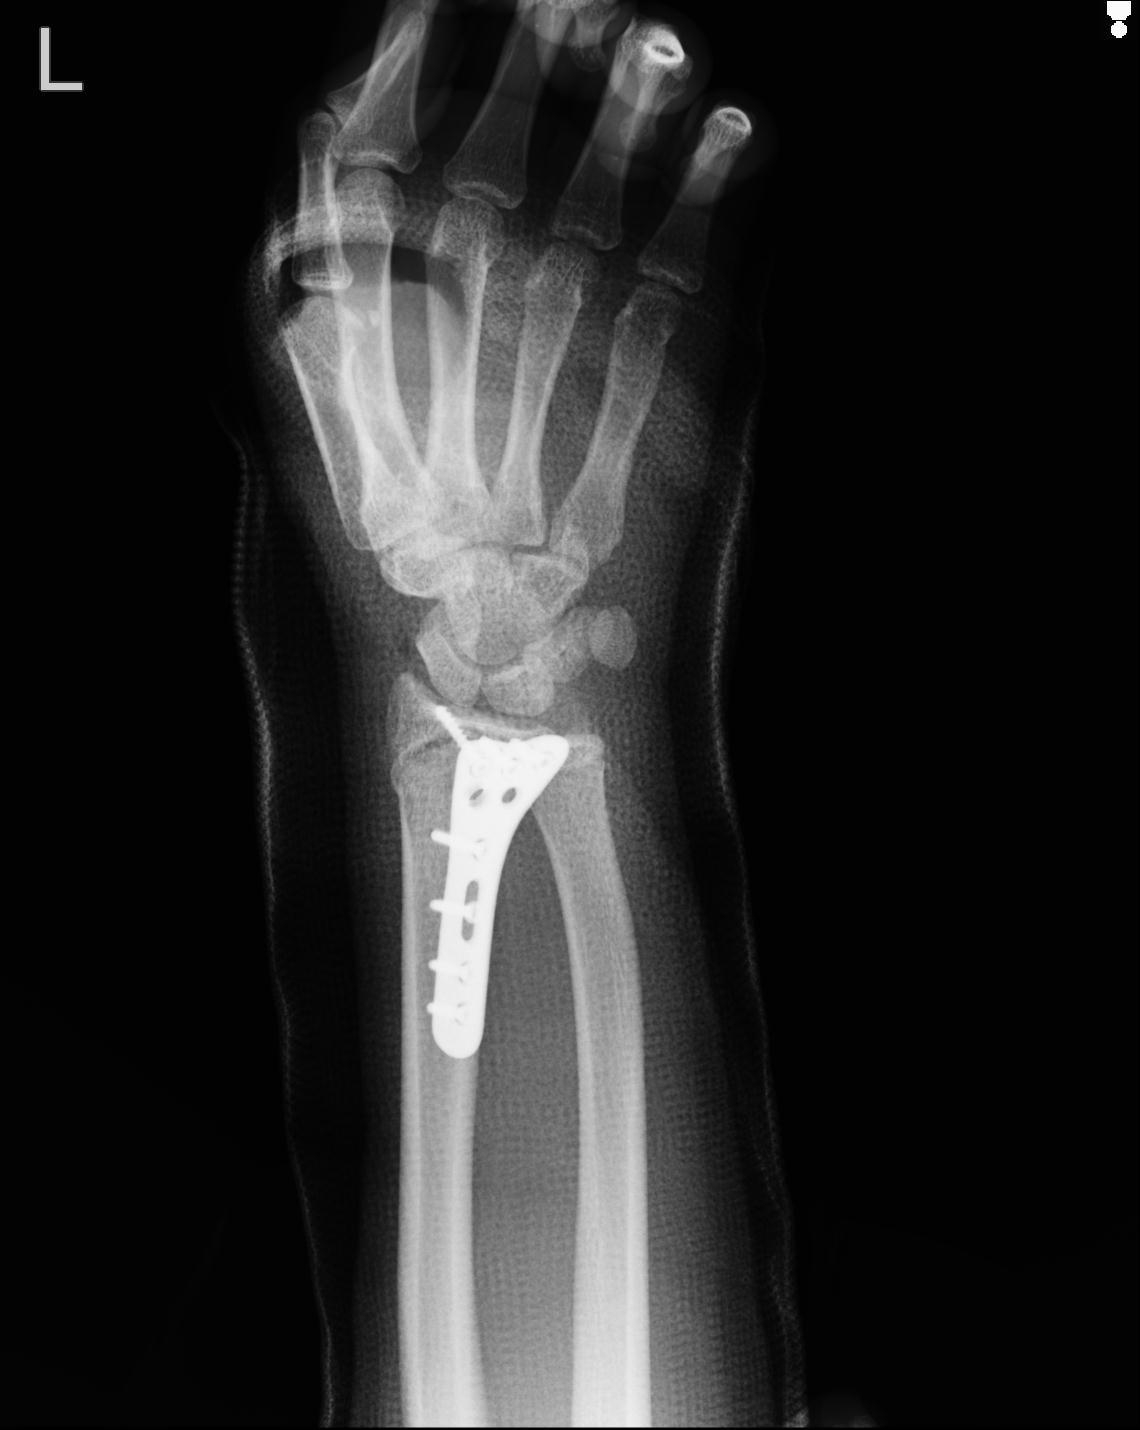

46666 1/23 両股正面+軸と右手関節 2R 76歳女性 右橈骨遠位端

46666 1/28 両股正面+軸と 1/26 右手関節 2R 76歳女性 右転子部骨折

50435 1/4 1/15 手関節 4R 17歳女性 右橈骨遠位端

102739 12/30 1/5 左手関節 4R 92歳女性 橈骨遠位端

101290 1/4 5/21 5/20 手関節 2R 17歳男性 橈骨遠位端